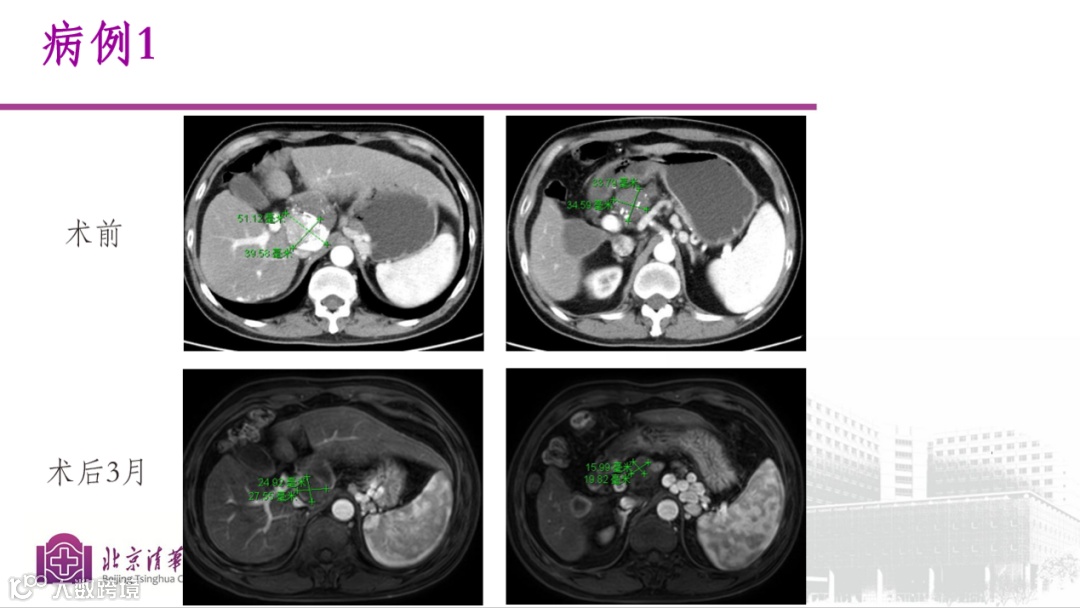

病例一